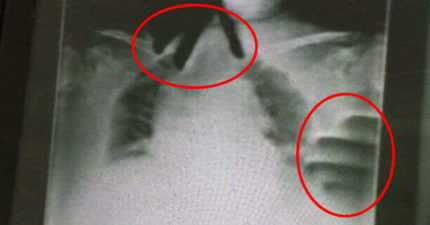

阿嬤住院突喘不過氣 X光驚現「無骨雙手掐脖」!主治醫出面證實了

February 25, 2023

台灣